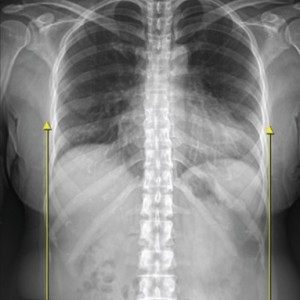

이제는 하세요!

엑스레이 검사

척추측만증 또는 좌, 우 한쪽으로 기울어진 척추로 인해 체중이 한쪽 허리로 집중된다면 장기적으로 체중이 기울어진 쪽 허리에 뼈가 자라거나 퇴행성 변화가 빠르게 진행됩니다.